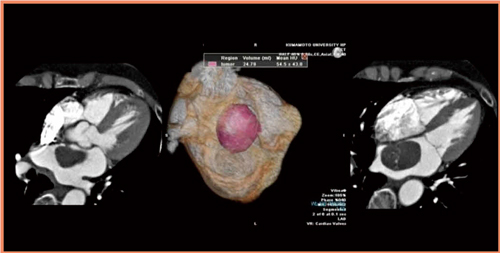

まず,ボリウムデータから腫瘍の大きさを測定し,Vitreaワークステーションを使って容量などを計測する(図5)。本症例も収縮期と拡張期の画像が必要と考え,R-R 30〜80%のデータをスキャンした。収縮期と拡張期の画像を比較してみると,左房前壁と腫瘍の間に見られたストーク状の構造に再現性がなく,腫瘍の付着部は心房中隔の卵円孔近傍であることがわかった。比較的典型的な粘液腫であると診断することができる(図6)。

図5 症例4:Vitreaワークステーションで腫瘍の容量を計測